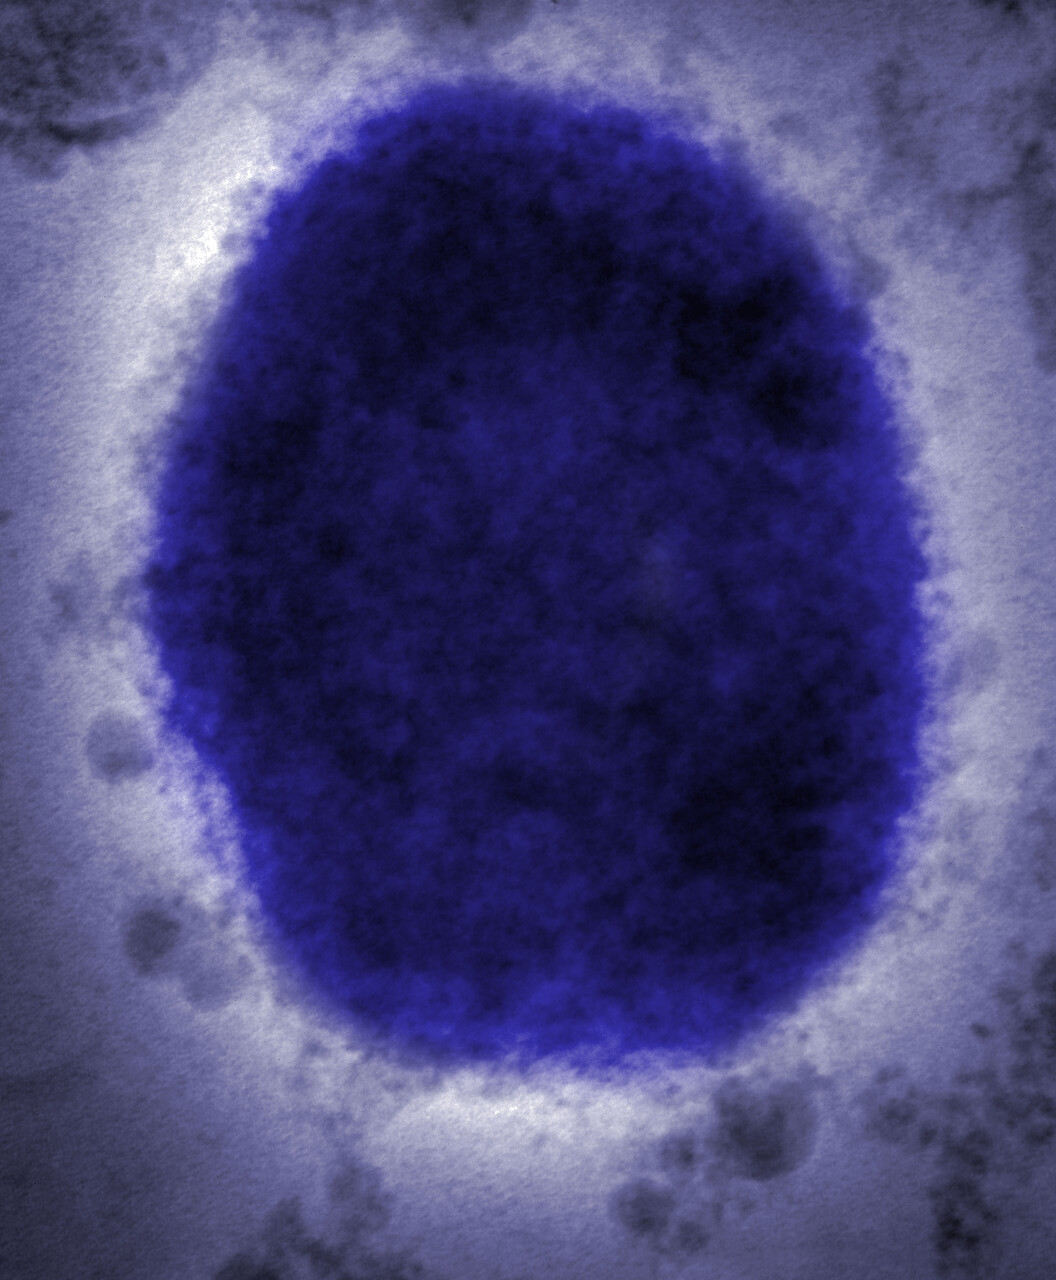

About mpox

Mpox is a disease that originally spread from animals to humans. It causes painful skin lesions, fever and muscle aches.